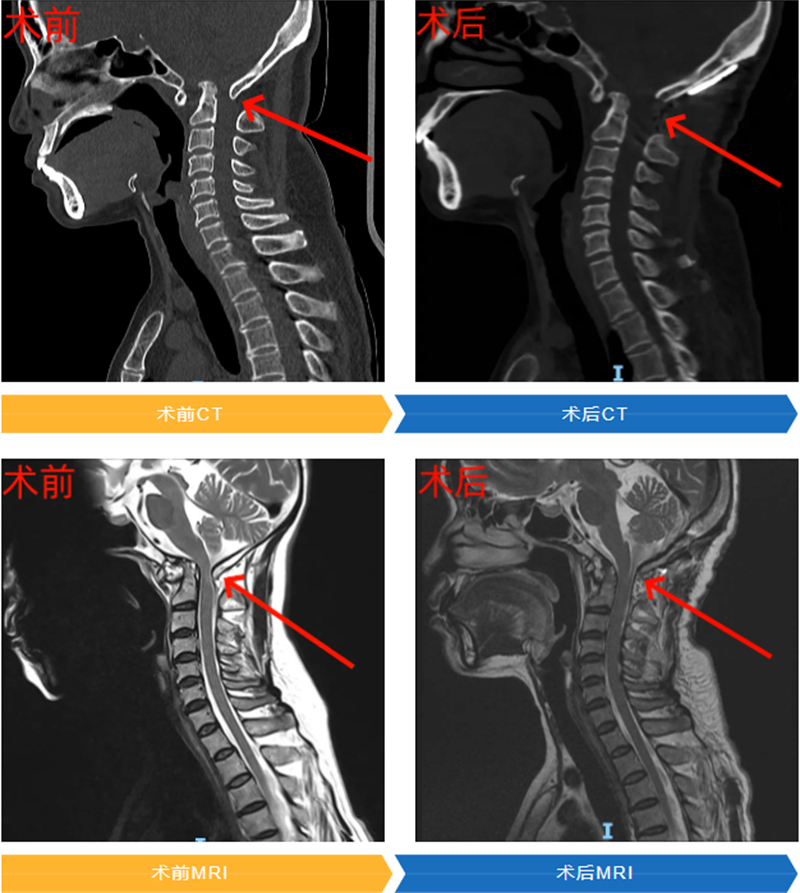

針對(duì)上述難點(diǎn),團(tuán)隊(duì)采用了代表當(dāng)前復(fù)雜顱頸交界畸形治療前沿的后路寰樞椎關(guān)節(jié)間撐開融合術(shù)。

該技術(shù)核心優(yōu)勢(shì)在于:通過單一后路切口即可完成關(guān)節(jié)松解、準(zhǔn)確復(fù)位、植入融合器并固定等所有關(guān)鍵步驟,避免了傳統(tǒng)前后路聯(lián)合手術(shù)的多重創(chuàng)傷、高感染風(fēng)險(xiǎn)及漫長(zhǎng)恢復(fù)期,體現(xiàn)微創(chuàng)精準(zhǔn)理念;融合器能維持復(fù)位后間隙,恢復(fù)解剖高度、解除神經(jīng)壓迫并提供植骨床,結(jié)合釘棒固定實(shí)現(xiàn)即刻穩(wěn)定與長(zhǎng)期融合,大幅降低復(fù)位丟失和再脫位風(fēng)險(xiǎn)。

術(shù)后,韋女士恢復(fù)情況令人欣喜。在脊柱外科醫(yī)護(hù)團(tuán)隊(duì)的精心治療與護(hù)理下,術(shù)后僅第三天,她就能在輔助下行走,長(zhǎng)期困擾的后頸部疼痛和肢體麻木等癥狀得到緩解。